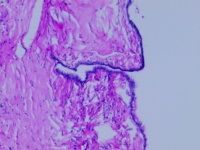

良性浆液性囊腺瘤?

性别

女

年龄

55岁

卵巢囊肿

浆液性囊腺瘤